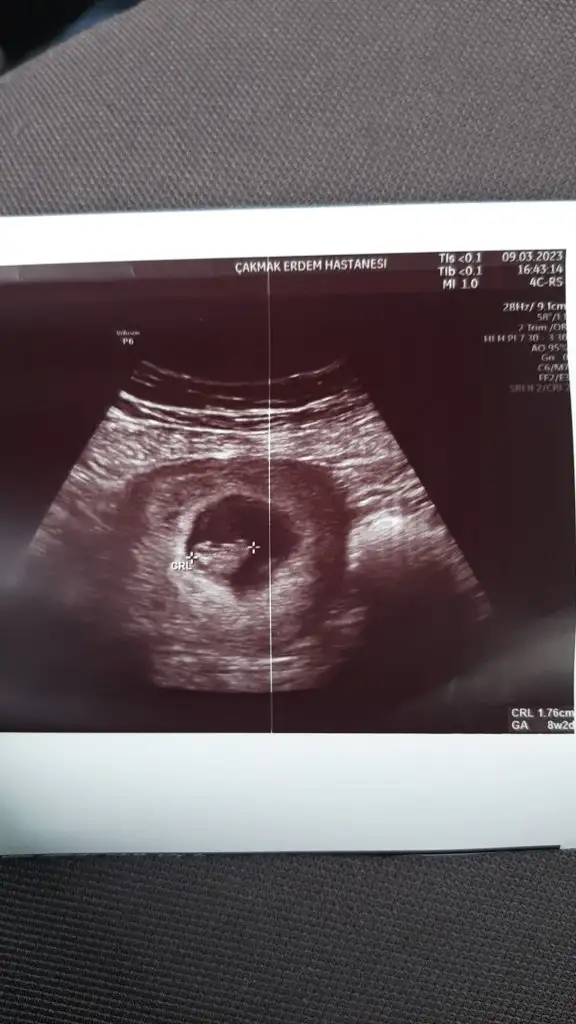

Bana da yorum yapar mısınızBu sekılde

Canim ben kiz olarak gordumBana da yorum yapar mısınız8+2